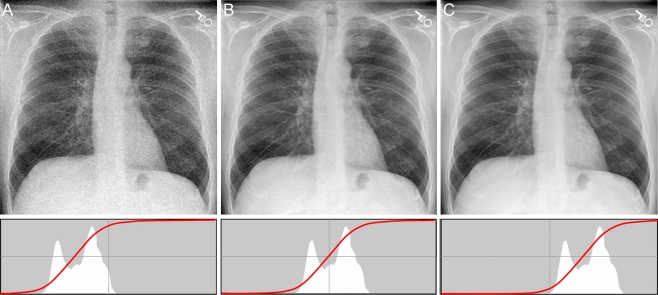

We can adjust the exposure of the images through proper windowing:

Here the windowing (or gray-level mapping) of the images, as indicated by the position of the red lines, improves the image contrast.